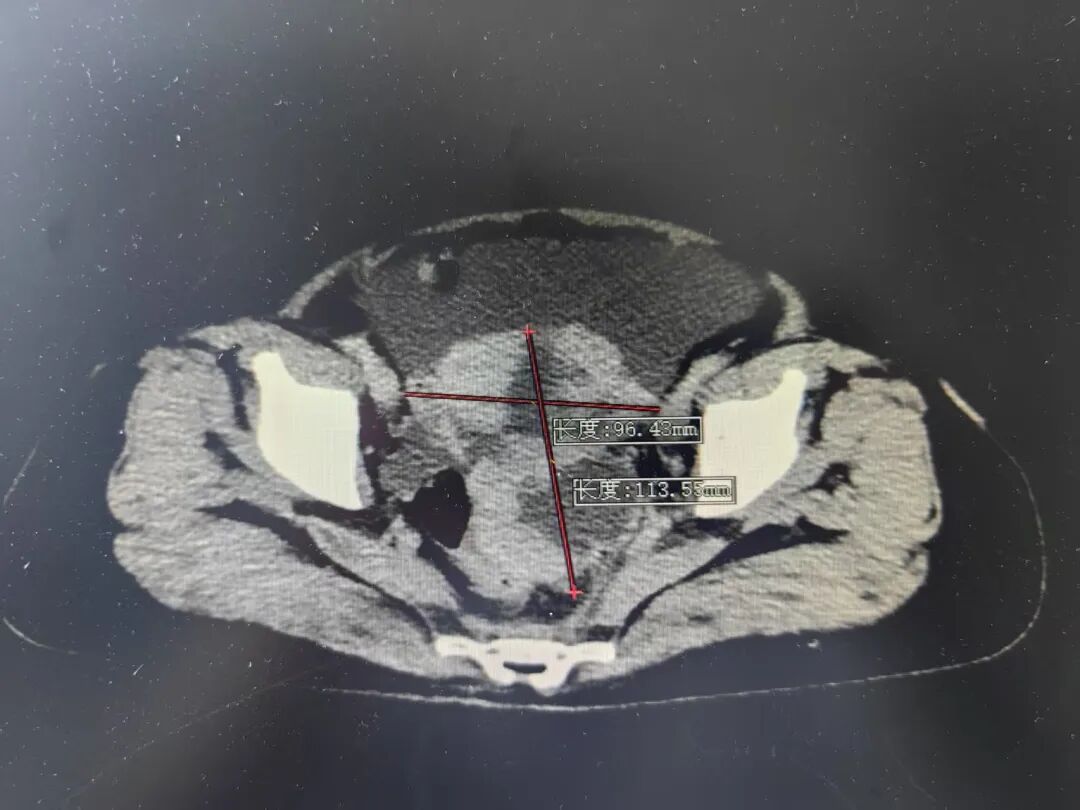

卵巢癌被称为“妇癌之王” 是妇科三大恶性肿瘤之一 可发生于任何年龄 早期症状隐蔽 晚期病例 缺乏有效的治疗手段 致死率居妇科恶性肿瘤的首位 53岁的张女士便不幸遭遇了这一“沉默杀手”。因腹痛、排便困难,来我院就诊时,CT检查发现卵巢肿瘤,强烈提示恶性可能,并存在广泛侵犯。 术前CT显示 因患者病情十分复杂,妇科专家团队立即启动多学科联合诊疗(MDT),综合研判认为,高度疑似晚期卵巢癌。考虑到立即手术难以实现满意的肿瘤细胞减灭,经患者及家属同意后,为其先行腹腔镜探查,获取病理诊断,确诊为:(腹膜、大网膜、肠系膜结节)转移性癌,符合卵巢浆液性癌来源,分期IIIC期。并制定2-3个疗程的新辅助化疗方案,为后续手术治疗创造有利条件。 恰逢重要契机,优质资源无缝对接: 在张女士进行手术治疗准备期间,时任珠海市人民医院副院长刘木彪率队莅临我院开展指导。珠海专家团队在详细了解到张女士的病情后,提出了进一步的治疗方案。 经过充分的前期准备并严格评估新辅助化疗效果,在珠海市人民医院妇科朱定军主任的指导下,我院妇科实施了剖腹探查术,成功减灭肿瘤细胞。术后,张女士继续接受规范化疗,三个月后,CT复查显示:盆腹腔未见病灶复发,肿瘤标记物显著下降。目前治疗仍在顺利进行中。 术后复查CT显示 张女士的经历揭示关键信息: 定期体检至关重要: 建议25岁以上的女性定期进行妇科检查及盆腔超声检查。 我院妇科与珠海市人民医院妇科建立了专科联盟合作关系。在此合作框架下,双方积极开展交流与协作,珠海市人民医院的妇科专家团队不定期前往我院开展门诊坐诊、教学查房、手术指导等工作,为贵州航天医院妇科肿瘤诊疗能力提升注入强劲动力。 贵州航天医院妇科 专家简介 邓桂林 妇科、耳鼻咽喉科党支部书记,妇科主任,主任医师 临床擅长:擅长妇科常见病、多发病的诊治,主攻方向妇科肿瘤,熟练掌握宫腔镜子宫肌瘤切除术、腹腔镜下子宫切除术、腹腔镜下早期宫颈癌根治术、子宫内膜癌分期手术、卵巢癌全面分期手术以及阴式手术等手术。 从事妇科专业医疗、教学及科研近20年,曾先后前往首都医科大学附属复兴医院、广州佛山市第一人民医院、重庆医科大学第一附属医院、遵义医科大学进修培训妇科内镜,通过CSCCP全国阴道镜规范化系列培训并获得GESEA证书;主持航天科工集团课题及遵义市科技局科研课题各1项,以第一作者发表学术论文10篇,参与编著著作2本,获专利6项。是中国初级卫生保健基金会妇科内分泌与辅助生殖专业委员会委员,中国优生优育协会妇产科专业委员会委员,中国医药教育协会更年期医学教育专业委员会委员,《妇儿健康导刊》杂志编委,中国中医药信息学会科学普及及分会第二届理事会理事,贵州省药学会妇产科疾病药物治疗专业委员会委员,贵州省医学会计划生育学分会第二届委员会委员,贵州省中西结合学会第二妇产专业委员会委员,贵州省中西结合学会第二届妇产专业委员会第一届绝经学组委员委员,贵州医科大学附属医院妇科更年期专科联盟委员,遵义市中西医结合学会妇产专业委员会第一届副主任委员,遵义市妇产科学会第一届委员会委员,遵义市妇产科学会妇科肿瘤学分会第一届委员会委员,遵义市预防接种异常反应调查诊断专家。 温小英 妇科主任医师 临床擅长:从事妇产科临床、科研、教学工作近30年,对妇科各类良、恶性肿瘤的开腹手术具有丰富的手术经验,开展腹腔镜及阴式手术10余年,擅长妇科常见疾病诊断治疗,尤其擅长女性生殖道炎症,内分泌疾病等治疗。 主持参与省、市级科研项目多项,发表科研论文10余篇。 卢 韦 妇科副主任医师,硕士研究生 临床擅长:从事妇产科临床、科研、教学工作17年,对妇科常见病,多发病及妇科肿瘤诊治具有丰富的临床经验,尤其擅长宫腹腔镜多种微创手术、阴式手术、妇科肿瘤手术等。 遵义市医学高等专科学校授课教师,亚太生殖大健康协会委员,中国医药教育协会生殖内分泌专业委员会委员,贵州省医学会“健康贵州行动”妇产科巡讲团团员,女性下尿路疾病及盆底功能障碍性疾病及专家联盟委员,中西医结合专家志愿者学会妇产科专业委员会委员;曾多次前往北京首都医科大学附属复兴医院、广州南方医科大学附属第一医院、重庆市妇幼保健院、贵阳市妇幼保健院、贵州医科大学附属医院、遵义医科大学附属医院进修学习及交流;发表国家核心期刊杂志及国家级普刊杂志10余篇,发明实用性专利3项,参与编写妇产科应用教材1部,主持及参与省、市级科研课题2项。 苏远华 妇科副主任医师,硕士研究生 临床擅长:外阴白斑、子宫腺肌病、妇科肿瘤及内分泌等疾病的诊治;手术擅长:腹腔镜、宫腔镜、阴式等微创手术;临床科研方向:外阴白斑及子宫腺肌病。 2009年毕业于遵义医学院临床医学。2009年7月至2012年7月于遵义医科大学附属医院参加妇产科专科医师规范化培训3年并结业。2012年8月至今在遵义市贵州航天医院妇科工作,从事妇科临床工作及教学工作10余年,曾多次评为年终优秀带教老师。2016年4月于北京复兴医院学习宫腹腔镜并取得培训合格资格证书;2018年7月至2019年1月于重庆西南医院进修妇科腹腔镜技术。申报立项及获得资金资助的省级课题1项,参与市级课题研究2项。曾参加遵义市腹腔镜操作技能比赛获得三等奖。发表国家医学论文核心期刊5篇,其中第一作者4篇、专家述评1篇,省级论文3篇;参与编著书籍1本。遵义市高等医科专业学校授课教师;遵义市中西医结合学会妇产科专业委员会第一届秘书;妇科肿瘤学分会第三届委员会青年委员。 贵州航天医院 妇科简介 基本情况 贵州航天医院妇科是集医疗、教学、科研于一体的综合性临床科室,共有医护人员27人,现有正高级职称2人,副高级职称2人,硕士研究生7人,开放床位30张,多次获得医院优秀教学科室、技术创新优秀科室、健康宣教优秀集体等荣誉称号。配备有阴道镜检查仪、阴道B超机、门诊宫腔检查镜、盆底治疗仪、宫颈微波治疗仪、低频脉冲治疗仪、中频脉冲治疗仪、红外线治疗仪以及永磁旋震治疗仪等先进设备。 专科特色 (一)宫腔镜手术 宫腔镜检查术,粘膜下子宫切除术,子宫内膜息肉切除术,子宫内膜切除术,宫腔黏连分离术,宫腔异物取出术,子宫纵膈切除术,宫颈瘢痕妊娠病灶清除术(冷刀,电切均可)。 (二)腹腔镜手术 早期宫颈癌根治术,子宫内膜期全面分期手术,早期卵巢癌全面分期手术,全子宫切除术,子宫肌瘤剔除术,单孔腹腔镜输卵管切除术及卵巢剔除术等妇科良性病变手术。 (三)盆底重建手术:阴式全子宫切除术 子宫脱垂、阴道前后壁合并膀胱及直肠脱垂等盆底脏器脱垂的修补术:经阴道骶棘韧带悬吊术,经腹腔镜子宫(阴道)骶骨悬吊术,针对压力性尿失禁的尿道中段折叠缝合术及TVT-O手术。 (四)外阴整形术 会阴整形术、小阴唇整形术及阴道缩紧术。 诊疗范围 科室业务范围涵盖普通妇科、妇科肿瘤、生殖整复、计划生育、生殖内分泌。 普通妇科:诊治外阴、阴道、宫颈、子宫、附件及盆腔的各种炎症及良性病变。 妇科肿瘤方面:开展经腹及经腹腔镜宫颈癌、子宫内膜癌、卵巢癌手术及术后化学治疗。 生殖整复方面:开展大、小阴唇整形、处女膜修复、阴道缩紧、宫颈成形、输卵管复通。 计划生育方面:保胎、流产、监测排卵、促排卵、上环、取环。 妇科内分泌方面:开展调经、围绝经期的激素替代治疗等,手术途径可行宫腔镜、腹腔镜(含单孔腹腔镜)、宫腹腔镜联合手术等。 门诊开展项目:产后盆底肌康复治疗,宫颈癌三级预防,宫颈炎症微波治疗,无痛宫腔镜,无痛人流,诊刮、取环等宫腔操作。